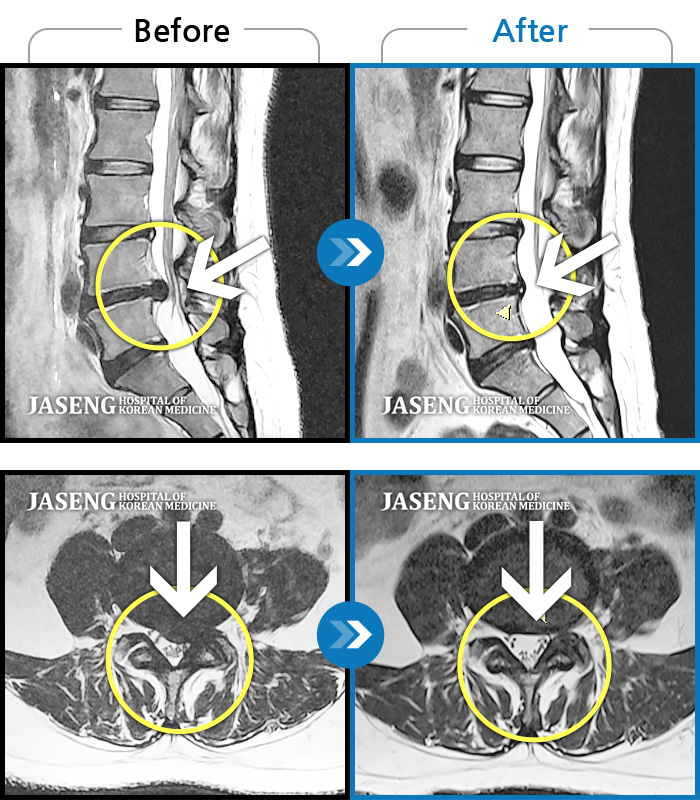

허리디스크

광주 · 김동은 원장

허리부터 골반 및 우측 허벅지에서 발가락까지 묵직한 통증과 저림 발생하여 내원하셨습니다.

촬영시기

2022.07.22 ~ 2025.08.18

2025.08.22